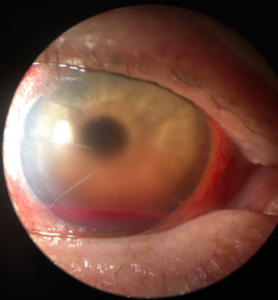

Anterior segment examination revealed unremarkable eyelids and eyelashes OU, significant hyperemia of the bulbar conjunctiva OD compared with a white and quiet bulbar conjunctiva OS. The cornea had stable cataract extraction and RK scars OU without Seidel sign, and RBCs on the inferior half of the corneal endothelium OD. The anterior chamber was deep and formed OU. There was a 1.5-mm hyphema OD with 3+ cell (mostly RBCs) and 3+ flare (Figure 1), while OS was quiet. There was poor visibility of the iris and lens OD, while OS had mild nasal iris atrophy and a clear, well-positioned PCIOL.

![]() Figure 1. External photo of the right eye at initial presentation: A 1.5-mm hyphema is visible in the inferior anterior chamber, and 3+ flare is obscuring the view of the pupil. The cornea has stable radial keratotomy scars with visible endothelial red blood cell staining on the inferior half. The conjunctiva has significant hyperemia. Eyelids and eyelashes are unremarkable. |